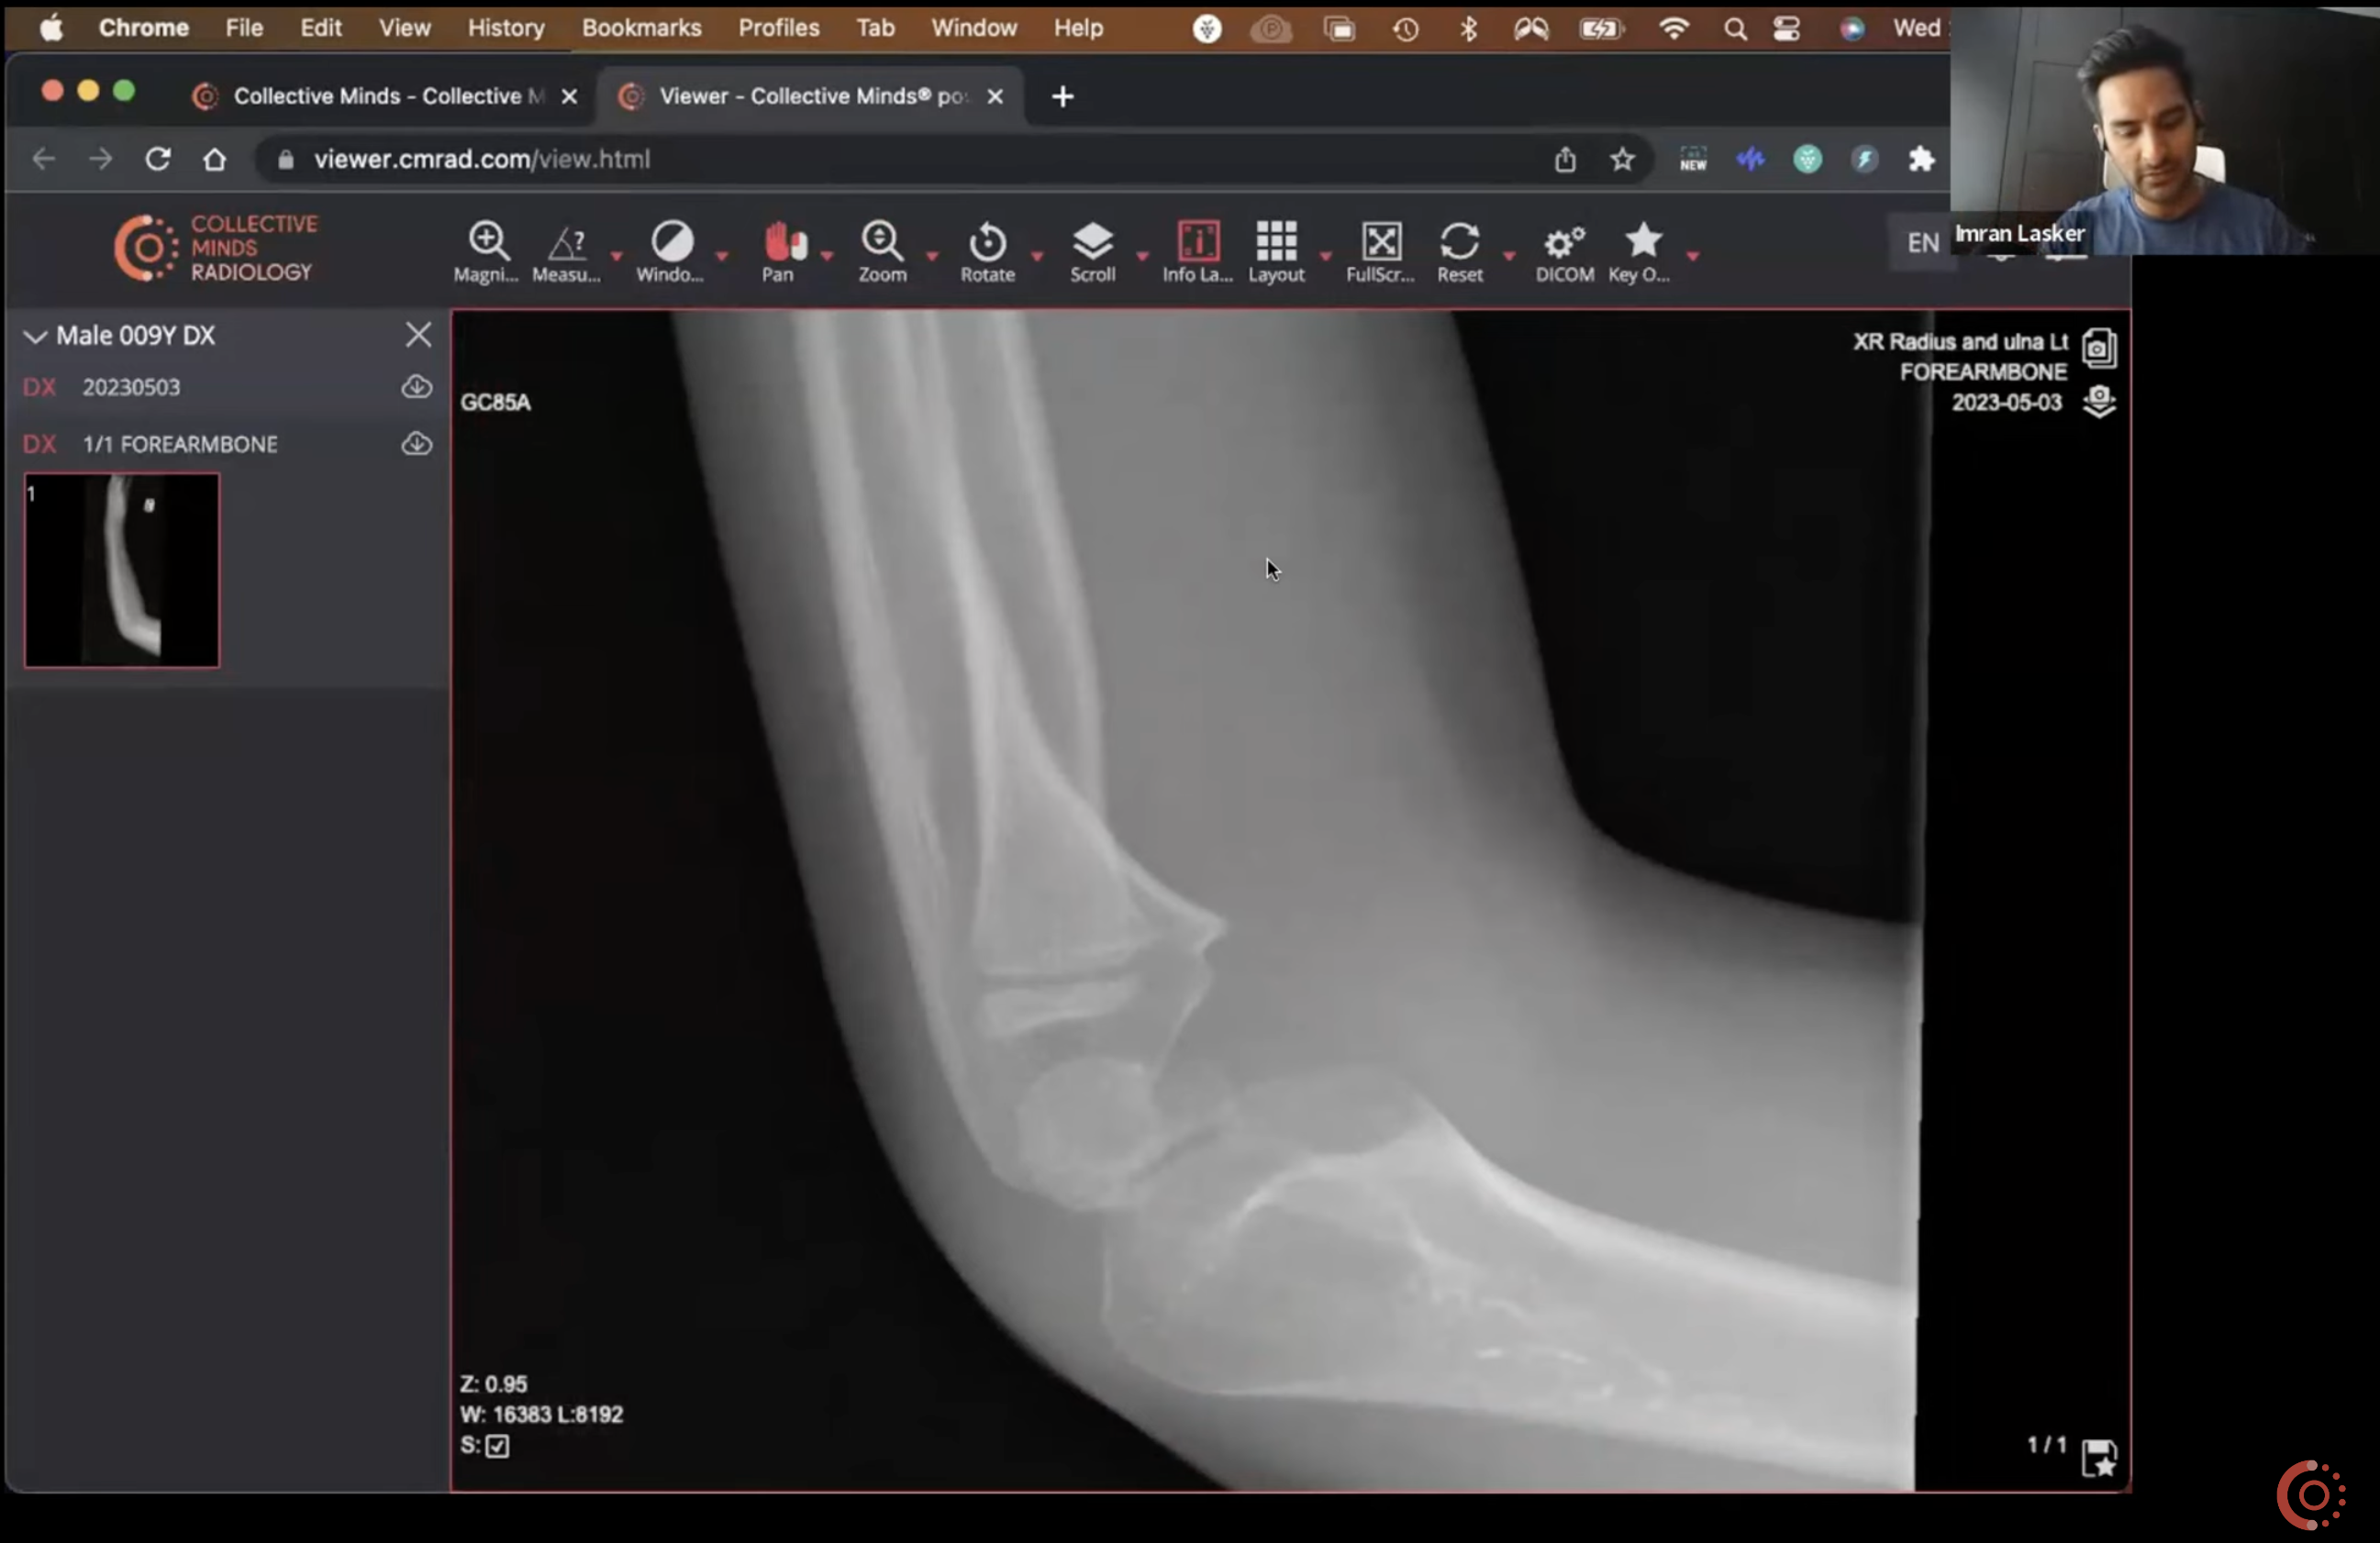

The course covers principles, techniques, and applications of imaging in evaluating musculoskeletal disorders. Students learn to interpret radiographic images, MRI, and CT scans, identifying normal anatomy, common pathologies, and imaging's role in diagnosis and treatment.